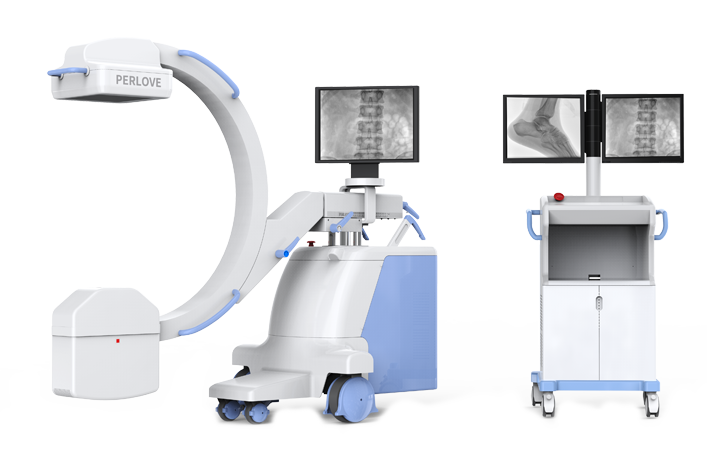

PLX118F系列

移动式平板C形臂X射线机

动态板C形臂 开启清晰影像新篇章 PLX118F

临床适用科室:骨科、普通外科、矫形外科、创伤外科、泌尿外科、脊柱外科、疼痛外科、消化科、妇科等科室。

大尺寸动态平板探测器,高DQE、低噪声、图像清晰。采用多分辨率图像增强处理技术,不同部位不同图像处理算法,满足客户多样化的需求。

采用智能变频脉冲透视技术,优化图像质量的同时降低辐射剂量,呵护医患健康

图形化操控界面设计:设有多种人体特征摄影参数,操作简便。双向红光十字定位系统:实现无射线下的高效定位。信息共享:遵循DICOM3.0格式接口,可无缝对接云PACS系统。

多角度自由旋转,满足患者复杂摆位需求。